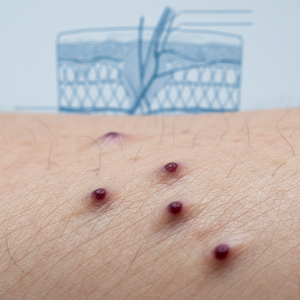

גידולים באשכים

אף על פי שזהו גורם פחות שכיח, נפיחות או גוש באשך עלולים להיות הסימן הראשון לסרטן האשכים. סוג סרטן זה פוגע בעיקר בגברים צעירים, בגילאי 15 עד 35. בדרך כלל, הגידול מתבטא כגוש קשה, לרוב ללא כאב, באחד האשכים, או כתחושת כבדות ונפיחות כללית.

לכן, כל גוש חדש באשך מחייב בדיקת אורולוג ללא דיחוי. החדשות הטובות הן שסרטן האשכים הוא אחד מסוגי הסרטן עם אחוזי הריפוי הגבוהים ביותר, במיוחד כאשר הוא מאובחן בשלב מוקדם. האבחון כולל בדיקה גופנית, אולטרסאונד אשכים ובדיקות דם לסמני גידול.